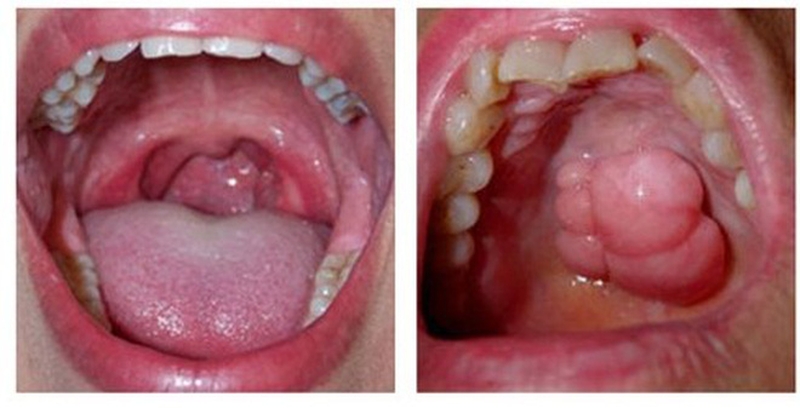

• Khối u, nốt gồ ghề, dày, vùng chợt nhỏ hoặc đóng vảy.

Tìm hiểu chung về ung thư xoang miệng2 Sự thay đổi màu sắc niêm mạc miệng (ví dụ những mảng trắng hoặc đỏ)

• Sự thay đổi màu sắc niêm mạc miệng (ví dụ những mảng trắng hoặc đỏ).